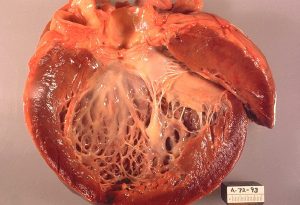

1. Dilated Cardiomyopathy:

The most common type, characterized by an enlarged and weakened heart chamber, which impairs the heart’s ability to pump blood. DCM can be inherited or caused by factors like chronic alcohol use, infections, or exposure to toxins.